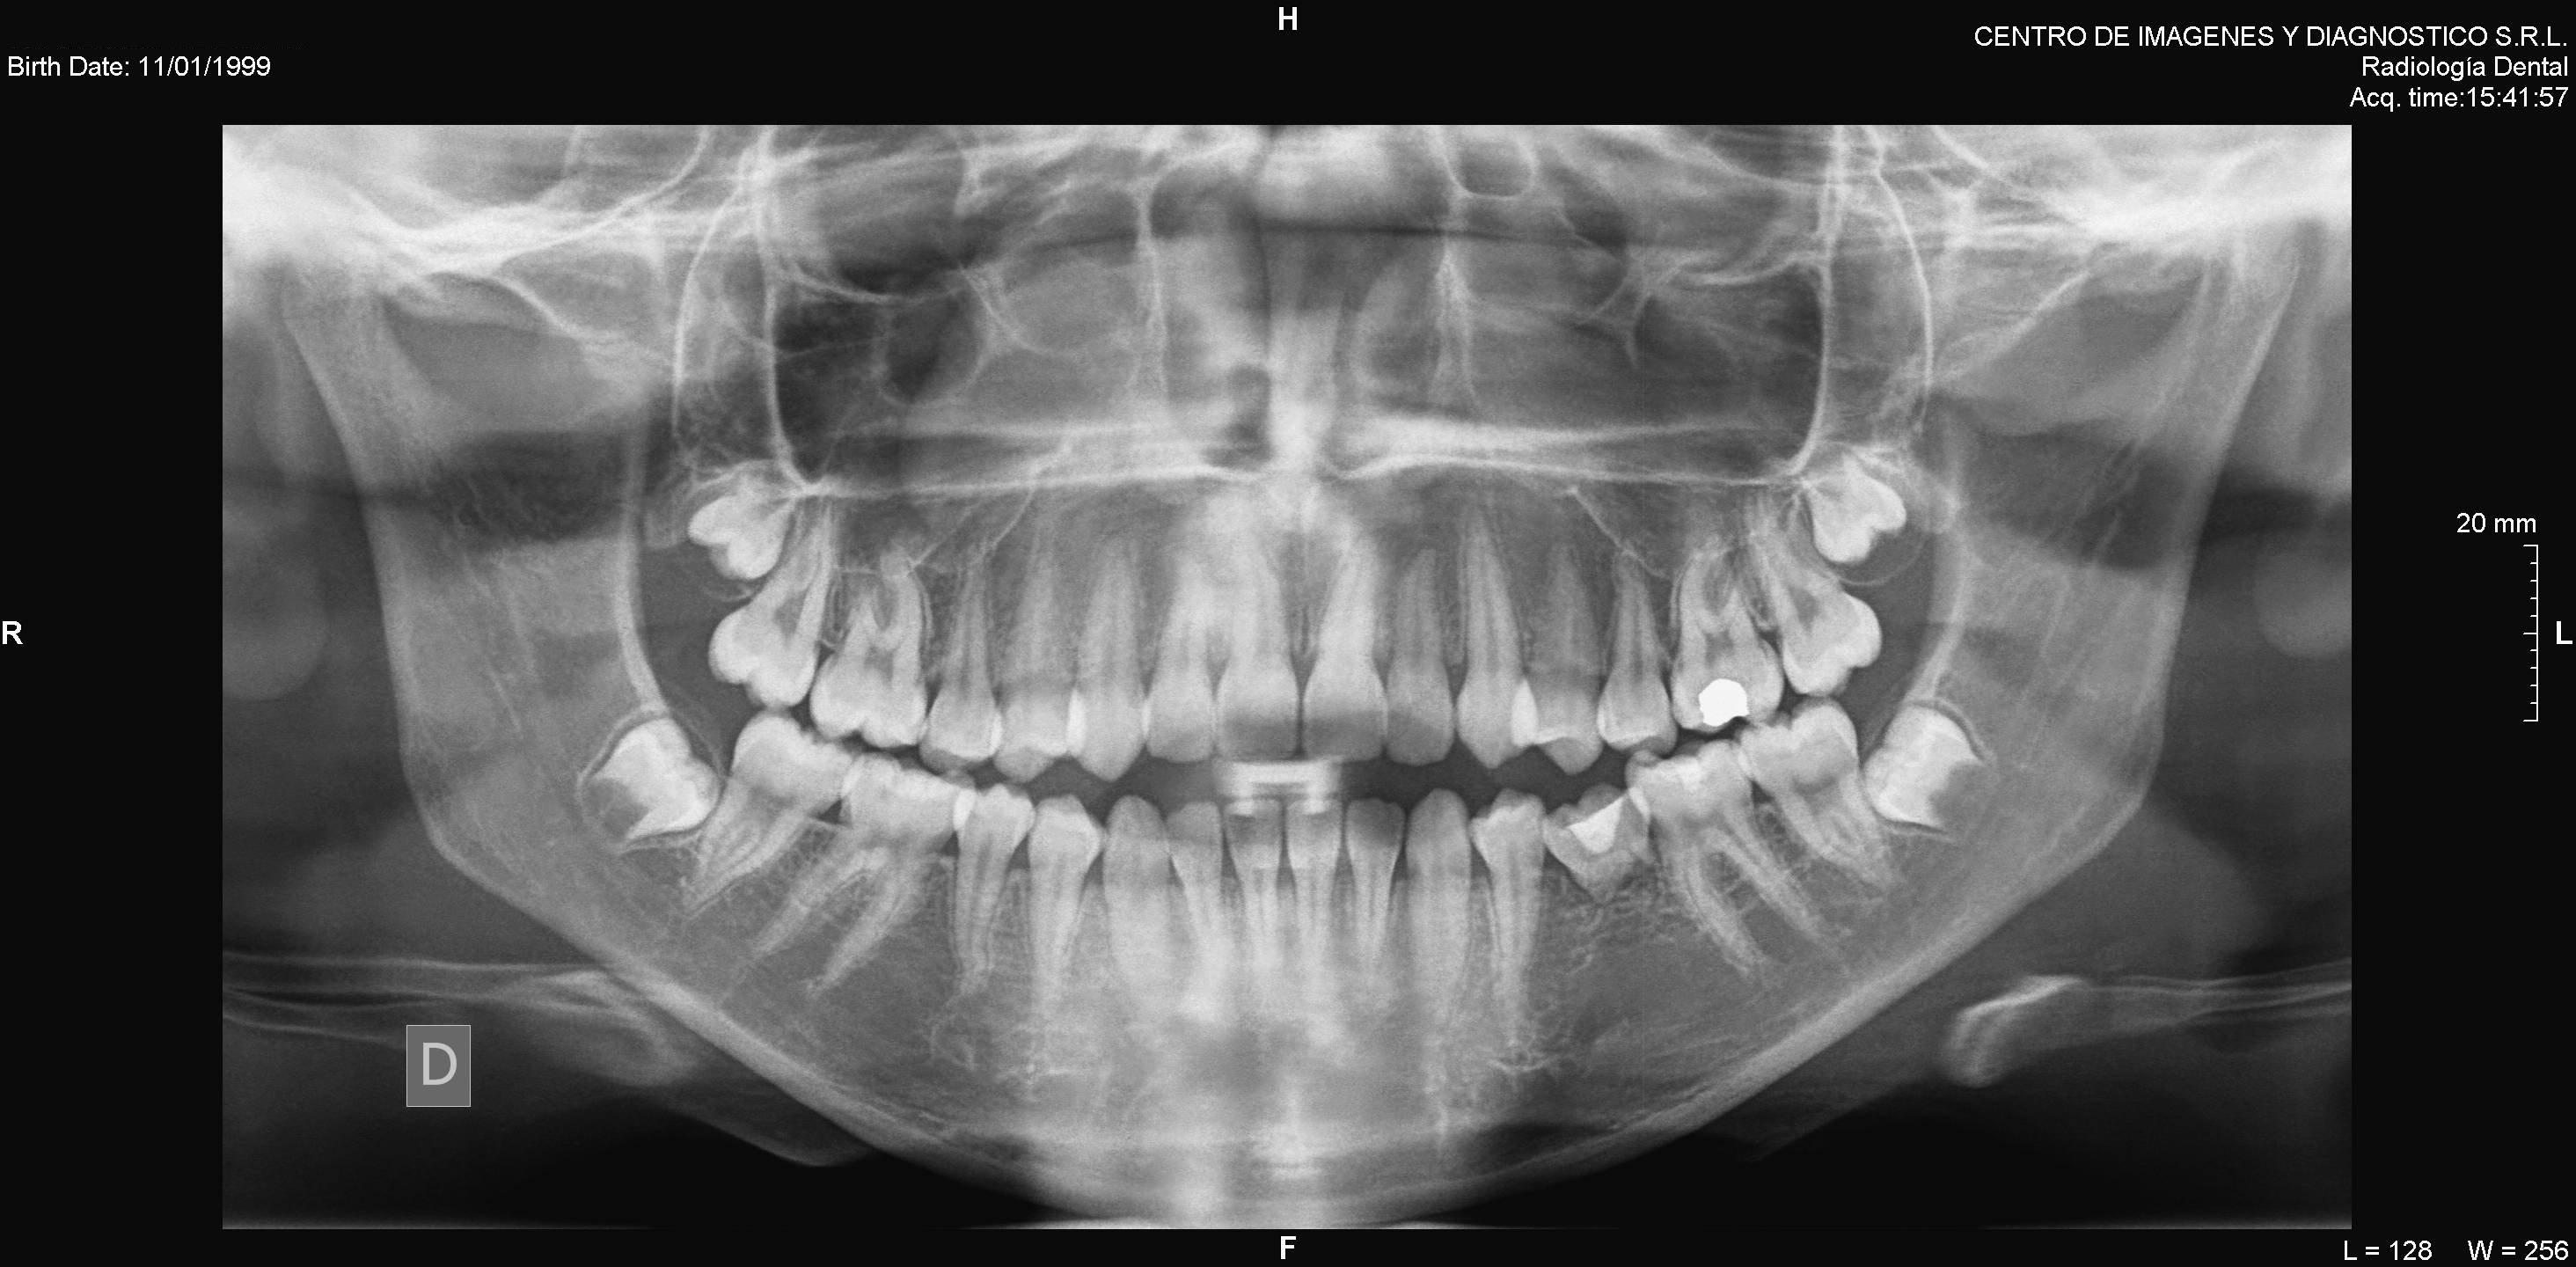

• Panorámica digital

Algunos ejemplos de imágenes digitales

Pulse en las imágenes para ver la ampliación

dientes